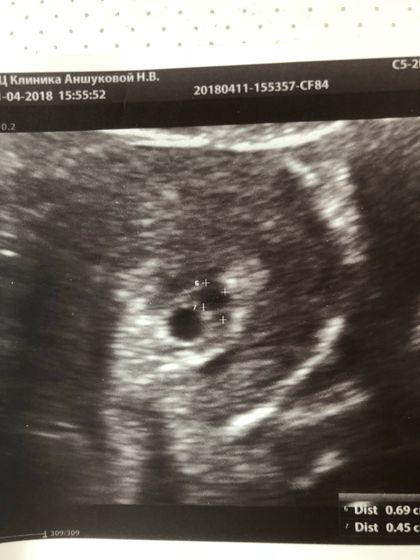

Привет девочки, вчера была на УЗИ, по Узи срок 4, нед и 6 дней. Ещё даже не видно эмбрион. Рядом с плодным яйцом круглое образование, врач сказала угроза Ретрохориальная гемотома, сморю на фото, и мысль покоя не даёт: может ли это быть второе плодное яйцо? Мог ли врачь ошибиться? Кто то сталкивался с такой проблемой?

Сказали плодное яйцо:7,5,5,7,8,9

Гематома 6,9на4,5мм

Вообще на плодное яйцо похоже, но какое-то оно не четкое. Белый ободок ровный должен быть. Гематома такая круглая чтобы была — первый раз вижу… сходите к другому специалисту на узи

Вообще если гематома на плодном яйце она не может быть такой идеально круглой ,,, она обычно полосочкой по переферии плодного яйца,,,

И на второе плодное яйцо не могу сказать похожа ли, так как не идеально ровный круг второй,,,